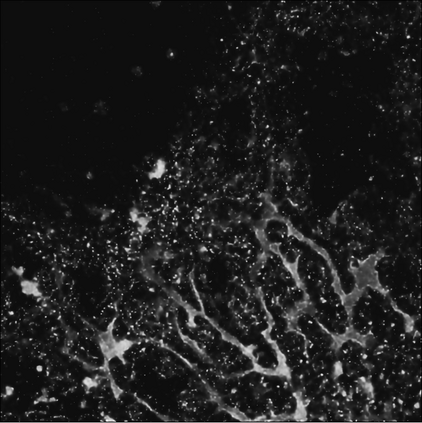

Motivated by the challenging segmentation task of pancreatic tubular networks, this paper tackles two commonly encountered problems in biomedical imaging: Topological consistency of the segmentation, and expensive or difficult annotation. Our contributions are the following: a) We propose a topological score which measures both topological and geometric consistency between the predicted and ground truth segmentations, applied to model selection and validation. b) We provide a full deep-learning methodology for this difficult noisy task on time-series image data. In our method, we first use a semisupervised U-net architecture, applicable to generic segmentation tasks, which jointly trains an autoencoder and a segmentation network. We then use tracking of loops over time to further improve the predicted topology. This semi-supervised approach allows us to utilize unannotated data to learn feature representations that generalize to test data with high variability, in spite of our annotated training data having very limited variation. Our contributions are validated on a challenging segmentation task, locating tubular structures in the fetal pancreas from noisy live imaging confocal microscopy. We show that our semi-supervised model outperforms not only fully supervised and pre-trained models but also an approach which takes topological consistency into account during training. Further, our approach achieves a mean loop score of 0.808 for detecting loops in the fetal pancreas, compared to a U-net trained with clDice with mean loop score 0.762.